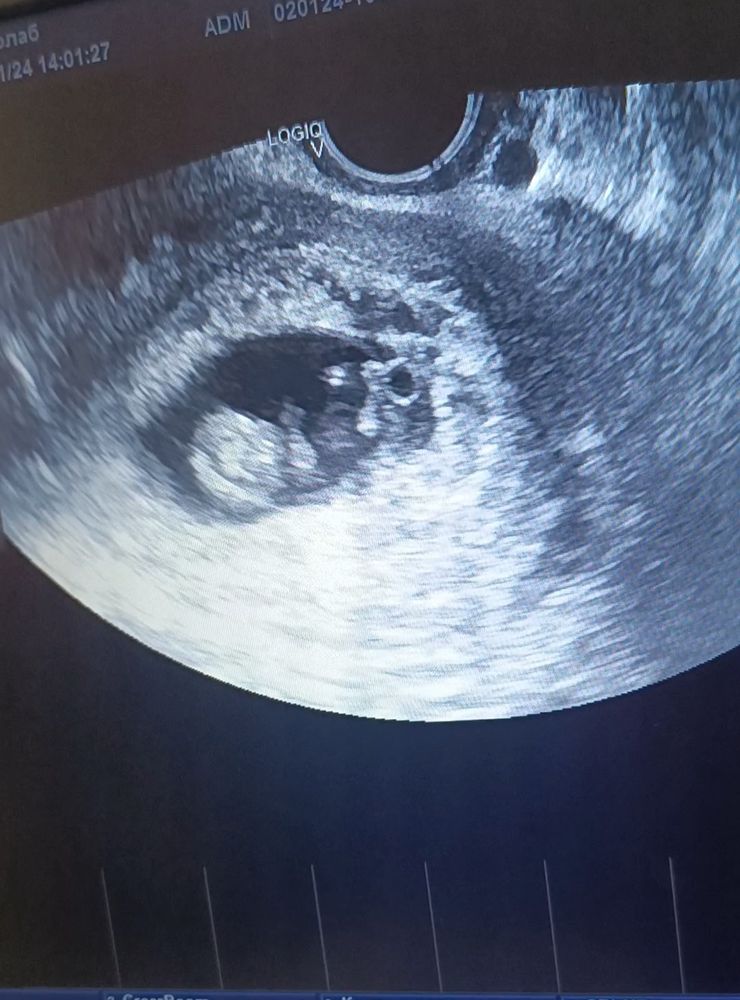

Мое

Мое плодное деформированное яйцо,при самостоятельной беременности,на тот момент ещё и с огромной отслойкой.фотка рядом результат который уже лежит рядом.не волнуйтесь.слушайте врачей.многие любят жути нагнать